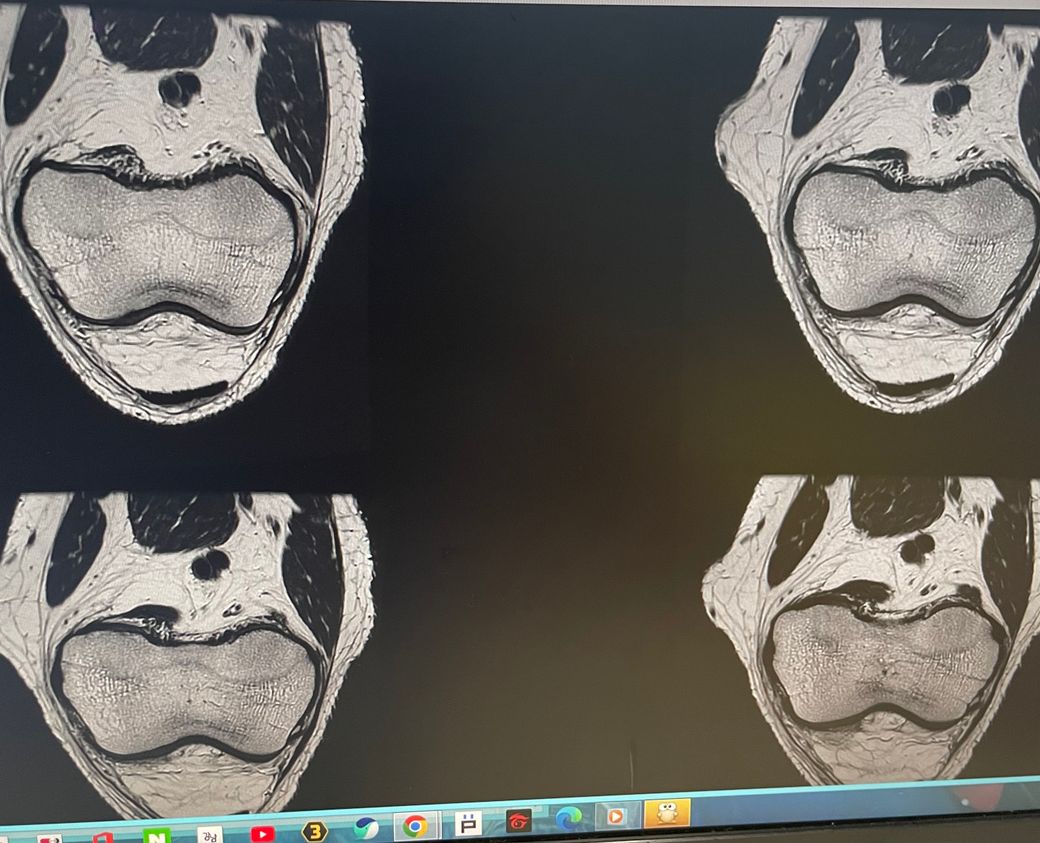

무릎 왼쪽 mri 사진 판독 부탁드리겠습니다.

안녕하세요 3달전쯤에 무릎을 다쳐서 약 한달전에 mri를 찍었습니다.

현재 판독상 인대나 반월연골 손상은 없는 것으로 판독지에 기재되어 있습니다. 임상적인 증상도 중요하니 담당의사와 상의하시고 신검시에 해당과 군의관 판정을 받으시는 것이 좋겠습니다.

십자인대에는 문제가 없지만 반월판의 문제가 있는 것으로 보입니다.

ACL 즉 전방 십자 인대에 불규칙한 소견은 있으나 Tear 즉 십자 인대가 파열되었다는

소견은 관찰되지 않는 상태이며 연골에 퇴행성 변화는 있는 것으로 보이나 이 역시 R/O

으로 확실하지 않음을 의미합니다. 결과적으로 십자 인대의 파열이 명확하지 않는 상태로

군대를 연기할 사유가 될지는 모르며 전방 십자 등 인대 손상의 경우는 명확하게 파열된

소견을 보이지 않는 경우, 군 입대에 문제가 되지는 않을 것으로 생각됩니다.